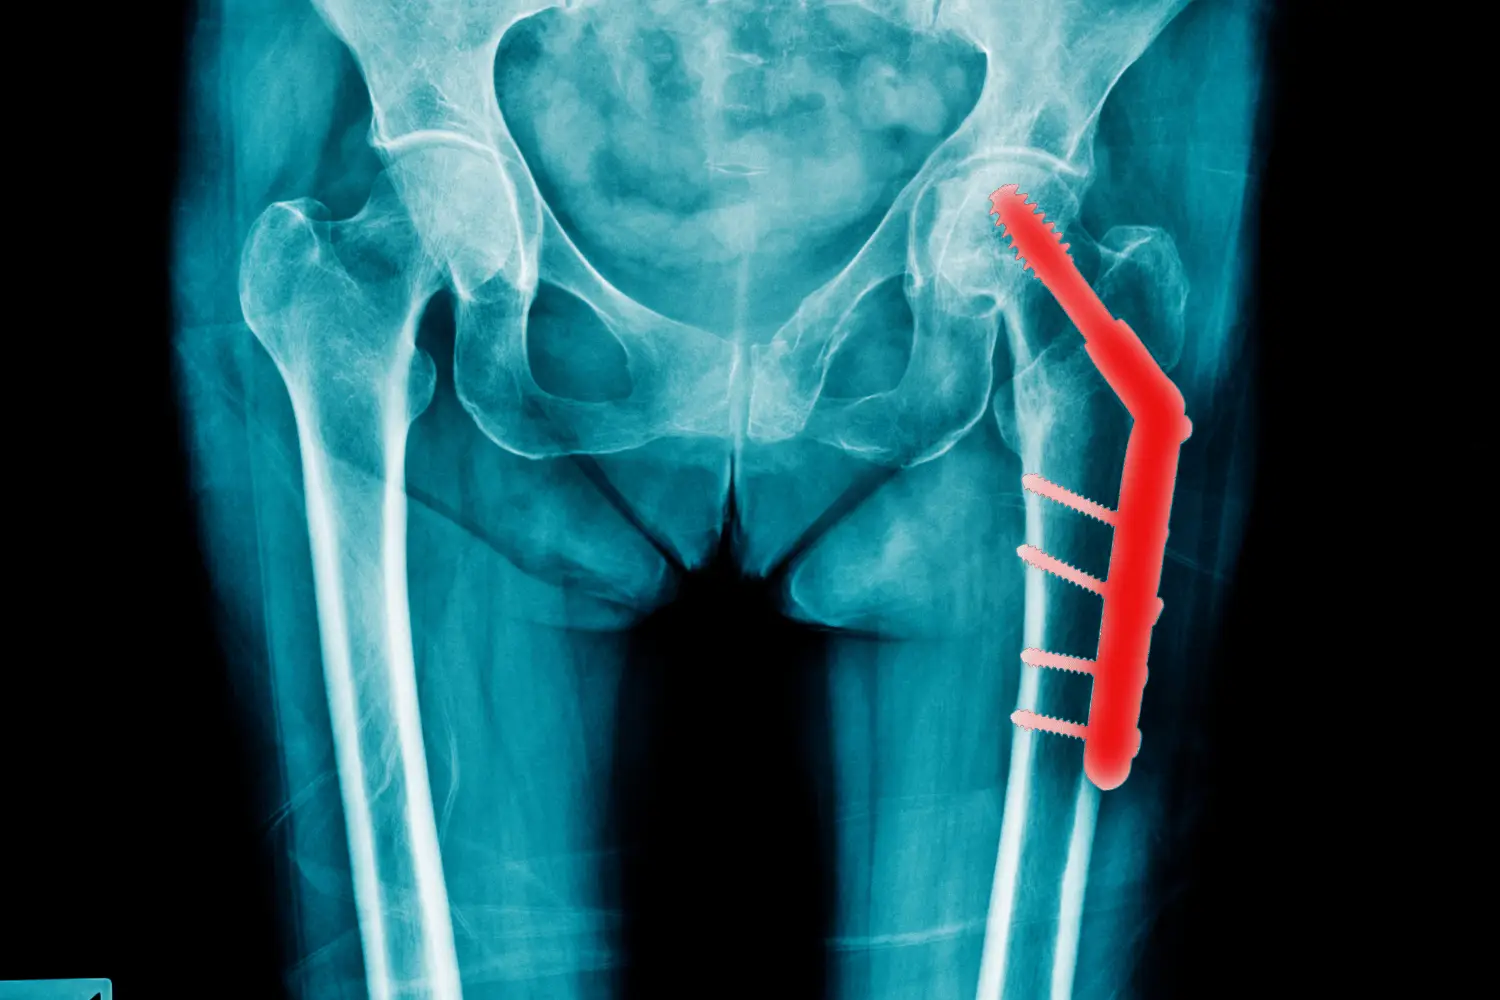

Fracture Treatment